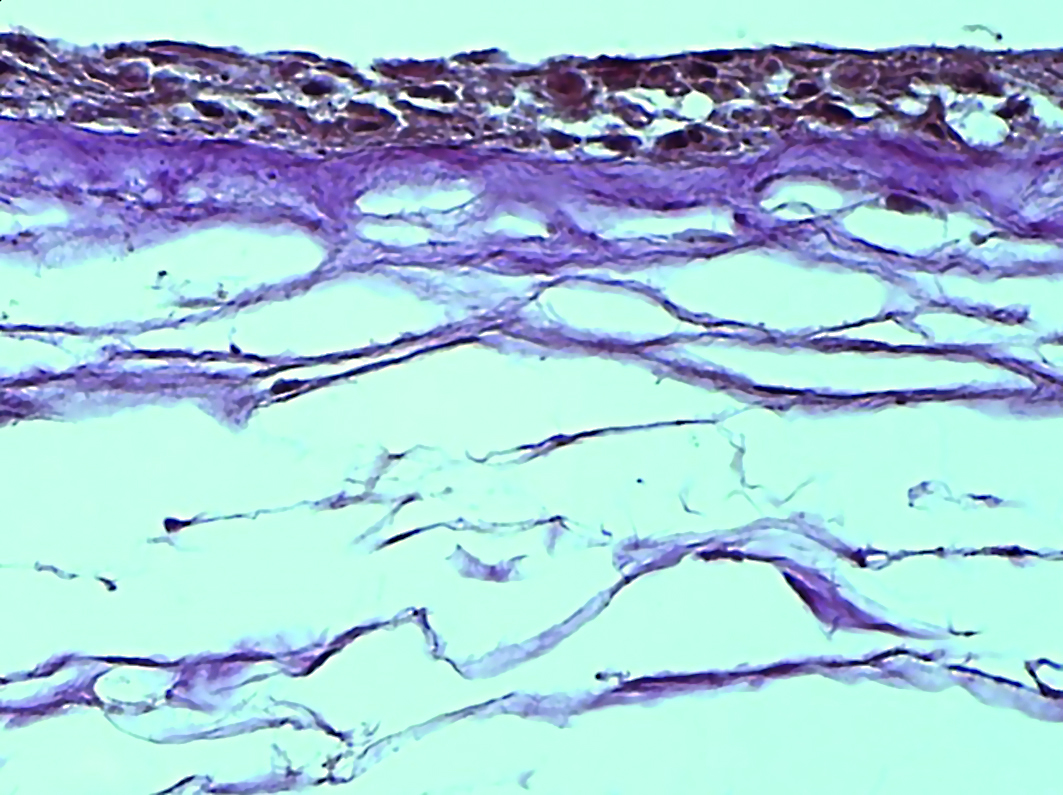

The spongy layer is represented with denser connective fibers, on which homogenous structure-less substrates are visualized, attached in clusters (Fig. 7).

Figure 7. Electron microscopic image of amniotic membrane in a scanning electron microscope. Spongy layer of a lyophilized amniotic membrane preparation with preliminary impregnation with glycerol. Magnification x400.

Рисунок 7. Электронно-микроскопическое изображение амниотической мембраны в сканирующем электронном микроскопе. Спонгиозный слой препарата лиофилизированной амниотической мембраны с предварительным пропитыванием глицерином. Ув. х400.